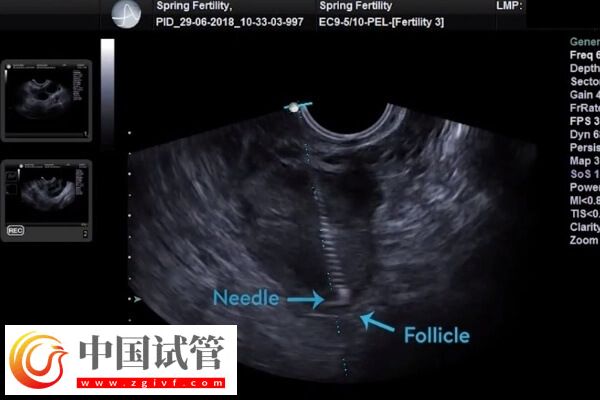

对于腹水较多且症状明显的患者,可在医生指导下进行穿刺引流,以快速排除腹水。在严重情况下,可能需要手术干预,如卵巢囊肿抽吸等。